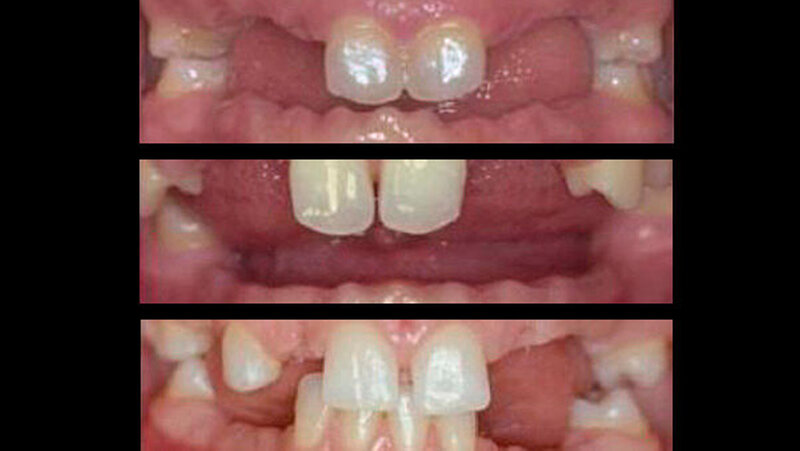

Als den Geschwistern genetisch bedingt die Milchzähne ausfielen, war die Familie zunächst geschockt: Alle drei Töchter hatten die Nichtanlage der bleibenden Zähne vom Vater geerbt. Denn die bleibenden Zähne kamen nicht. Nur einige wenige waren überhaupt angelegt.

Aufgrund der Krankheit fehlten nach dem Verlust der Milchzähne bei den Kindern insgesamt 54 Zähne und ein erheblicher Teil des Ober- und Unterkieferknochens. Normales Kauen war unmöglich. Professionelle Hilfe kam vom erfahrenen MKG-Chirurgenteam: Mit Knochentransplantaten konnten der Ober- und Unterkiefer als „Fundament“ für spätere Zahnimplantate aufgebaut - also augmentiert - werden.

Zunächst entfernten die MKG-Chirurgen alle vorhandenen Milchzähne. Nach einer Abheilungsphase von rund zwölf Wochen wurde aufgrund der ausgeprägten Alveolarkammatrophie die umfangreiche horizontale Augmentation im Ober- und Unterkiefer mit körpereigenem Knochen vom Becken in Allgemeinnarkose durchgeführt. Nach sechs weiteren Monaten wurden insgesamt 43 Implantate inseriert und weitere drei Monate später erfolgte die Freilegung und das Weichteilmanagement.